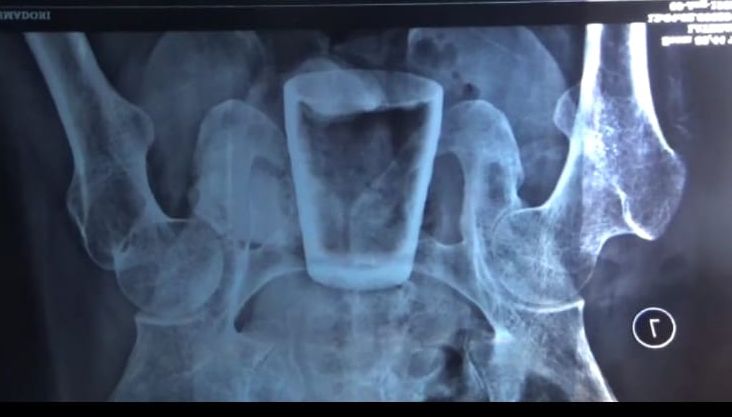

Karena kondisi yang tidak kunjung membaik ini, oleh mantri dirinya disarankan untuk melakukan rontgen. Hasilnya mengejutkan, karena didalam perutnya terdapat sebuah gelas bersarang dengan bagian atasnya pecah.

“Kami mendapat laporan dari salah satu relawan, jika mas Nur Lasidi warga Desa Sidomulyo mengalami sakit aneh, kemudian saya datangi dan melihat hasil rontgennya, karena yang bersangkutan tidak memiliki kartu jaminan apa-apa, akhirnya kami turun koordinasi dengan Pemkab Jember untuk membawa yang bersangkutan ke RSD Balung guna menjalani operasi,” ujar Indriyati.